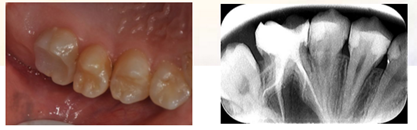

问诊信息:患者李某,女,15岁

主诉:左上后牙进食疼痛3月余

现病史:3月前左上后牙偶有进食疼痛,伴冷热刺激疼痛,无自发痛史,未予治疗,因影响进食来我院求治。

检查:26冠部大面积龋损,仅余近中颊侧残壁,残余牙体颜色变暗,牙龈增生至缺损牙体组织内部,髓腔内炎性牙髓组织增生呈息肉状。探诊(+),冷诊(±),叩诊(-),无松动。

X-ray示:26远中低密度影已穿通髓腔,与近中低密度影几近相连。根尖无低密度影像。

诊断:26慢性牙髓炎